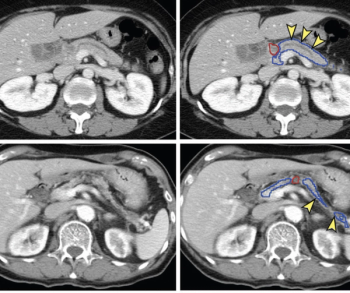

In the newly released Lung-RADS 2022 classification system for computed tomography (CT) lung cancer screening, the American College of Radiology (ACR) has noted a variety of updates including new classification criteria for atypical pulmonary cysts and airway nodules, time intervals for nodule growth and a new stepped management approach for Lung-RADS categories 3 and 4A.